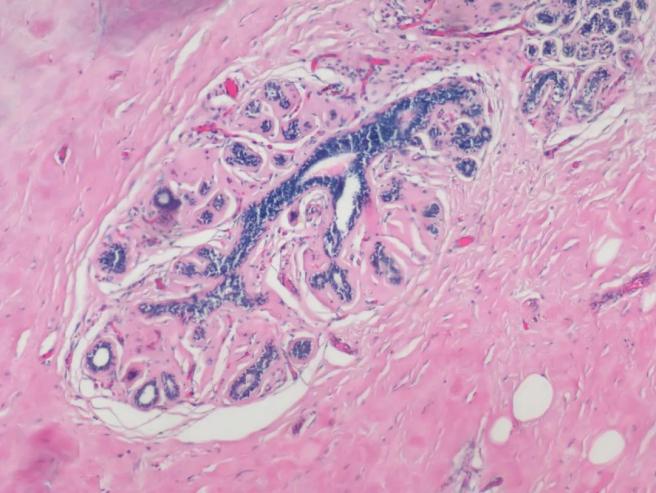

明美生物显微镜搭载高分辨率MSX2相机,可清晰呈现HE染色病理切片的细胞细节(如乳腺癌样本中蓝色的细胞核与红色的胞质),帮助快速识别癌细胞形态特征,为精准诊断提供可靠依据。

明美生物显微镜搭配msx2拍摄HE染色的乳腺癌病理切片,红色为胞质,蓝色为染色体